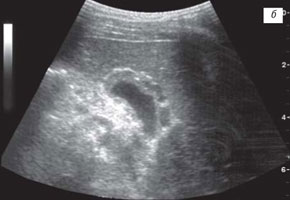

б) При тяжелым течении муковисцидоза.

Независимо от тяжести течения муковисцидоза аномалии развития желчного пузыря в виде различных перегибов: в области дна, тела, воронки, а также "S-образная" форма наблюдались у 18 детей. У 14 пациентов в просвете пузыря определялась "взвесь", у 3 детей - неполные перегородки в области шейки пузыря, у 3 детей старшего возраста имели место множественные конкременты размером от 6 до 12 мм. Стенки желчного пузыря были утолщены до 4 мм у 6 детей старшего возраста и до 2 мм - у 10 пациентов. У 5 детей с тяжелым течением муковисцидоза утолщение стенок желчного пузыря составило от 6 до 14 мм и у 2 из них определялся варикоз сосудов его стенок (рис. 1 б).